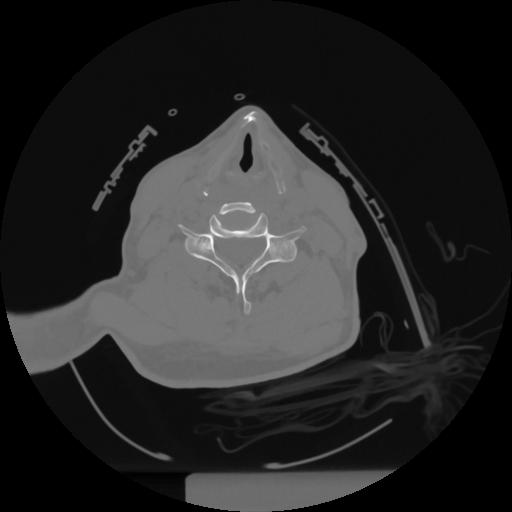

12 P.BLANDAS,,Vol,0.5,P.BLANDAS,,